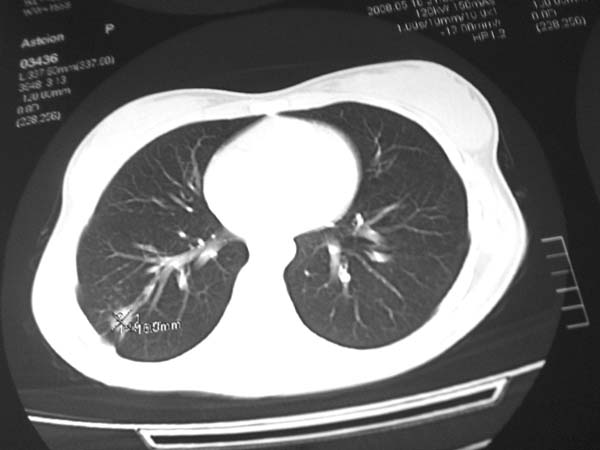

标题: CT13486:F 17Y 咳嗽 咳痰数日请会诊 [打印本页]

标题: CT13486:F 17Y 咳嗽 咳痰数日请会诊

白细胞9600不发烧

考虑为:右肺下叶外基底段结核球。

结果;痰中找到结核杆菌

痰涂片已找到结核杆菌  将结果告诉大家